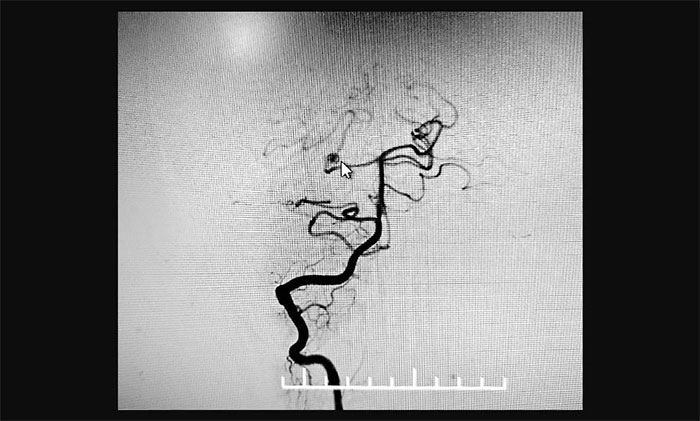

最终,在麻醉科团队及导管室介入团队的密切配合和监护下,神经外科于耀宇主任团队历时2小时,为王女士顺利实施脑血管造影+颅内动脉瘤栓塞术。术中,DSA造影确诊右侧小脑上动脉夹层动脉瘤,动脉瘤瘤体大小约为4x3 mm。术中,于耀宇主任凭借娴熟的技术,克服血管迂曲等困难,将栓塞导管成功送入夹层动脉瘤内,最终顺利栓塞夹层动脉瘤。术后,再次造影未见动脉瘤显影,见远端分支显影良好,“炸弹”危险被成功解除。术后,患者顺利苏醒,无神经功能障碍。

▲ 栓塞前